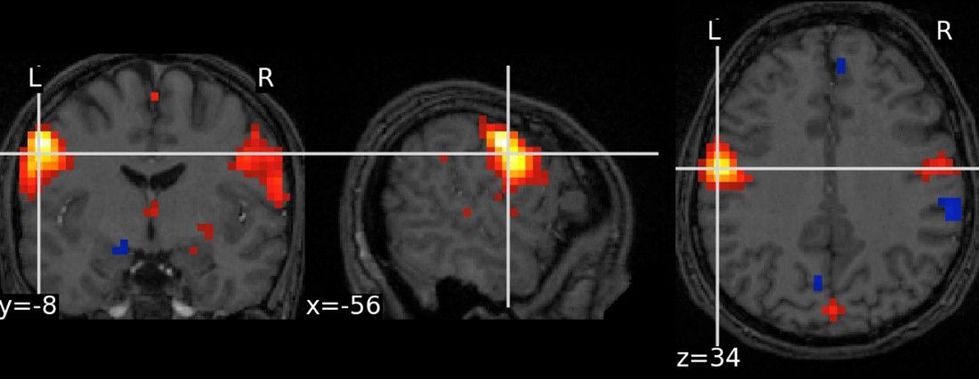

Figure 2 Visualization of brain networks from 3D dual regression volumes.